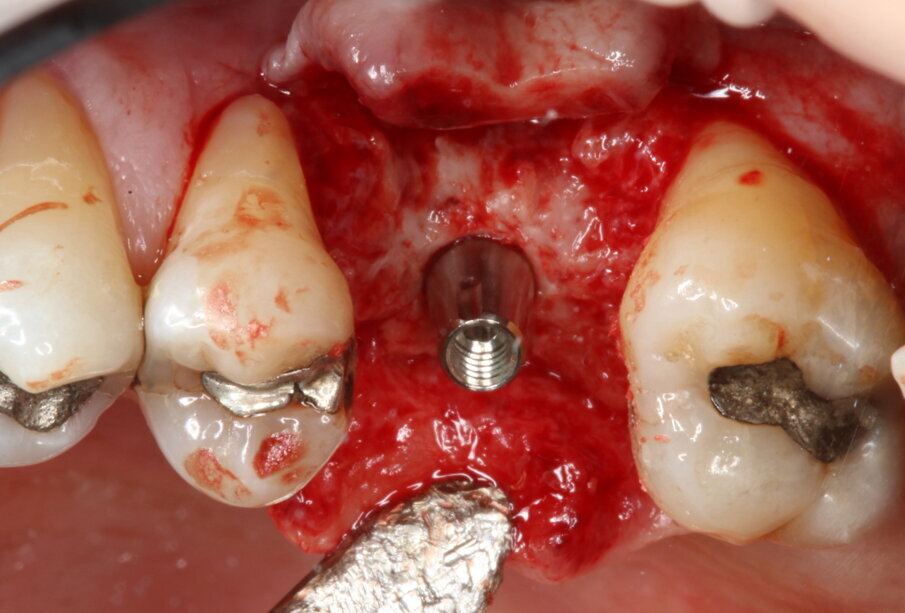

Posizionamento implantare

È stato inserito un impianto tronco-conico di 10 mm di lunghezza e 4,2 mm di diametro (AoN SLC con connessione Revcon) con torque di inserzione di 35 N e valori di ISQ pari a 66 in direzione vestibolo-linguale e 68 in direzione mesio-distale20. È stato applicato un moncone conometrico dritto e avvitato a 35 N con relativa cappa di guarigione in peek21 (Figg. 4, 5).

Fig. 3_Inserimento del biomateriale OsteoBiol Putty.

Fig. 4_Inserimento dell’impianto (AoN SLC con connessione Revcon).

Fig. 5_Applicazione del moncone conometrico dritto.